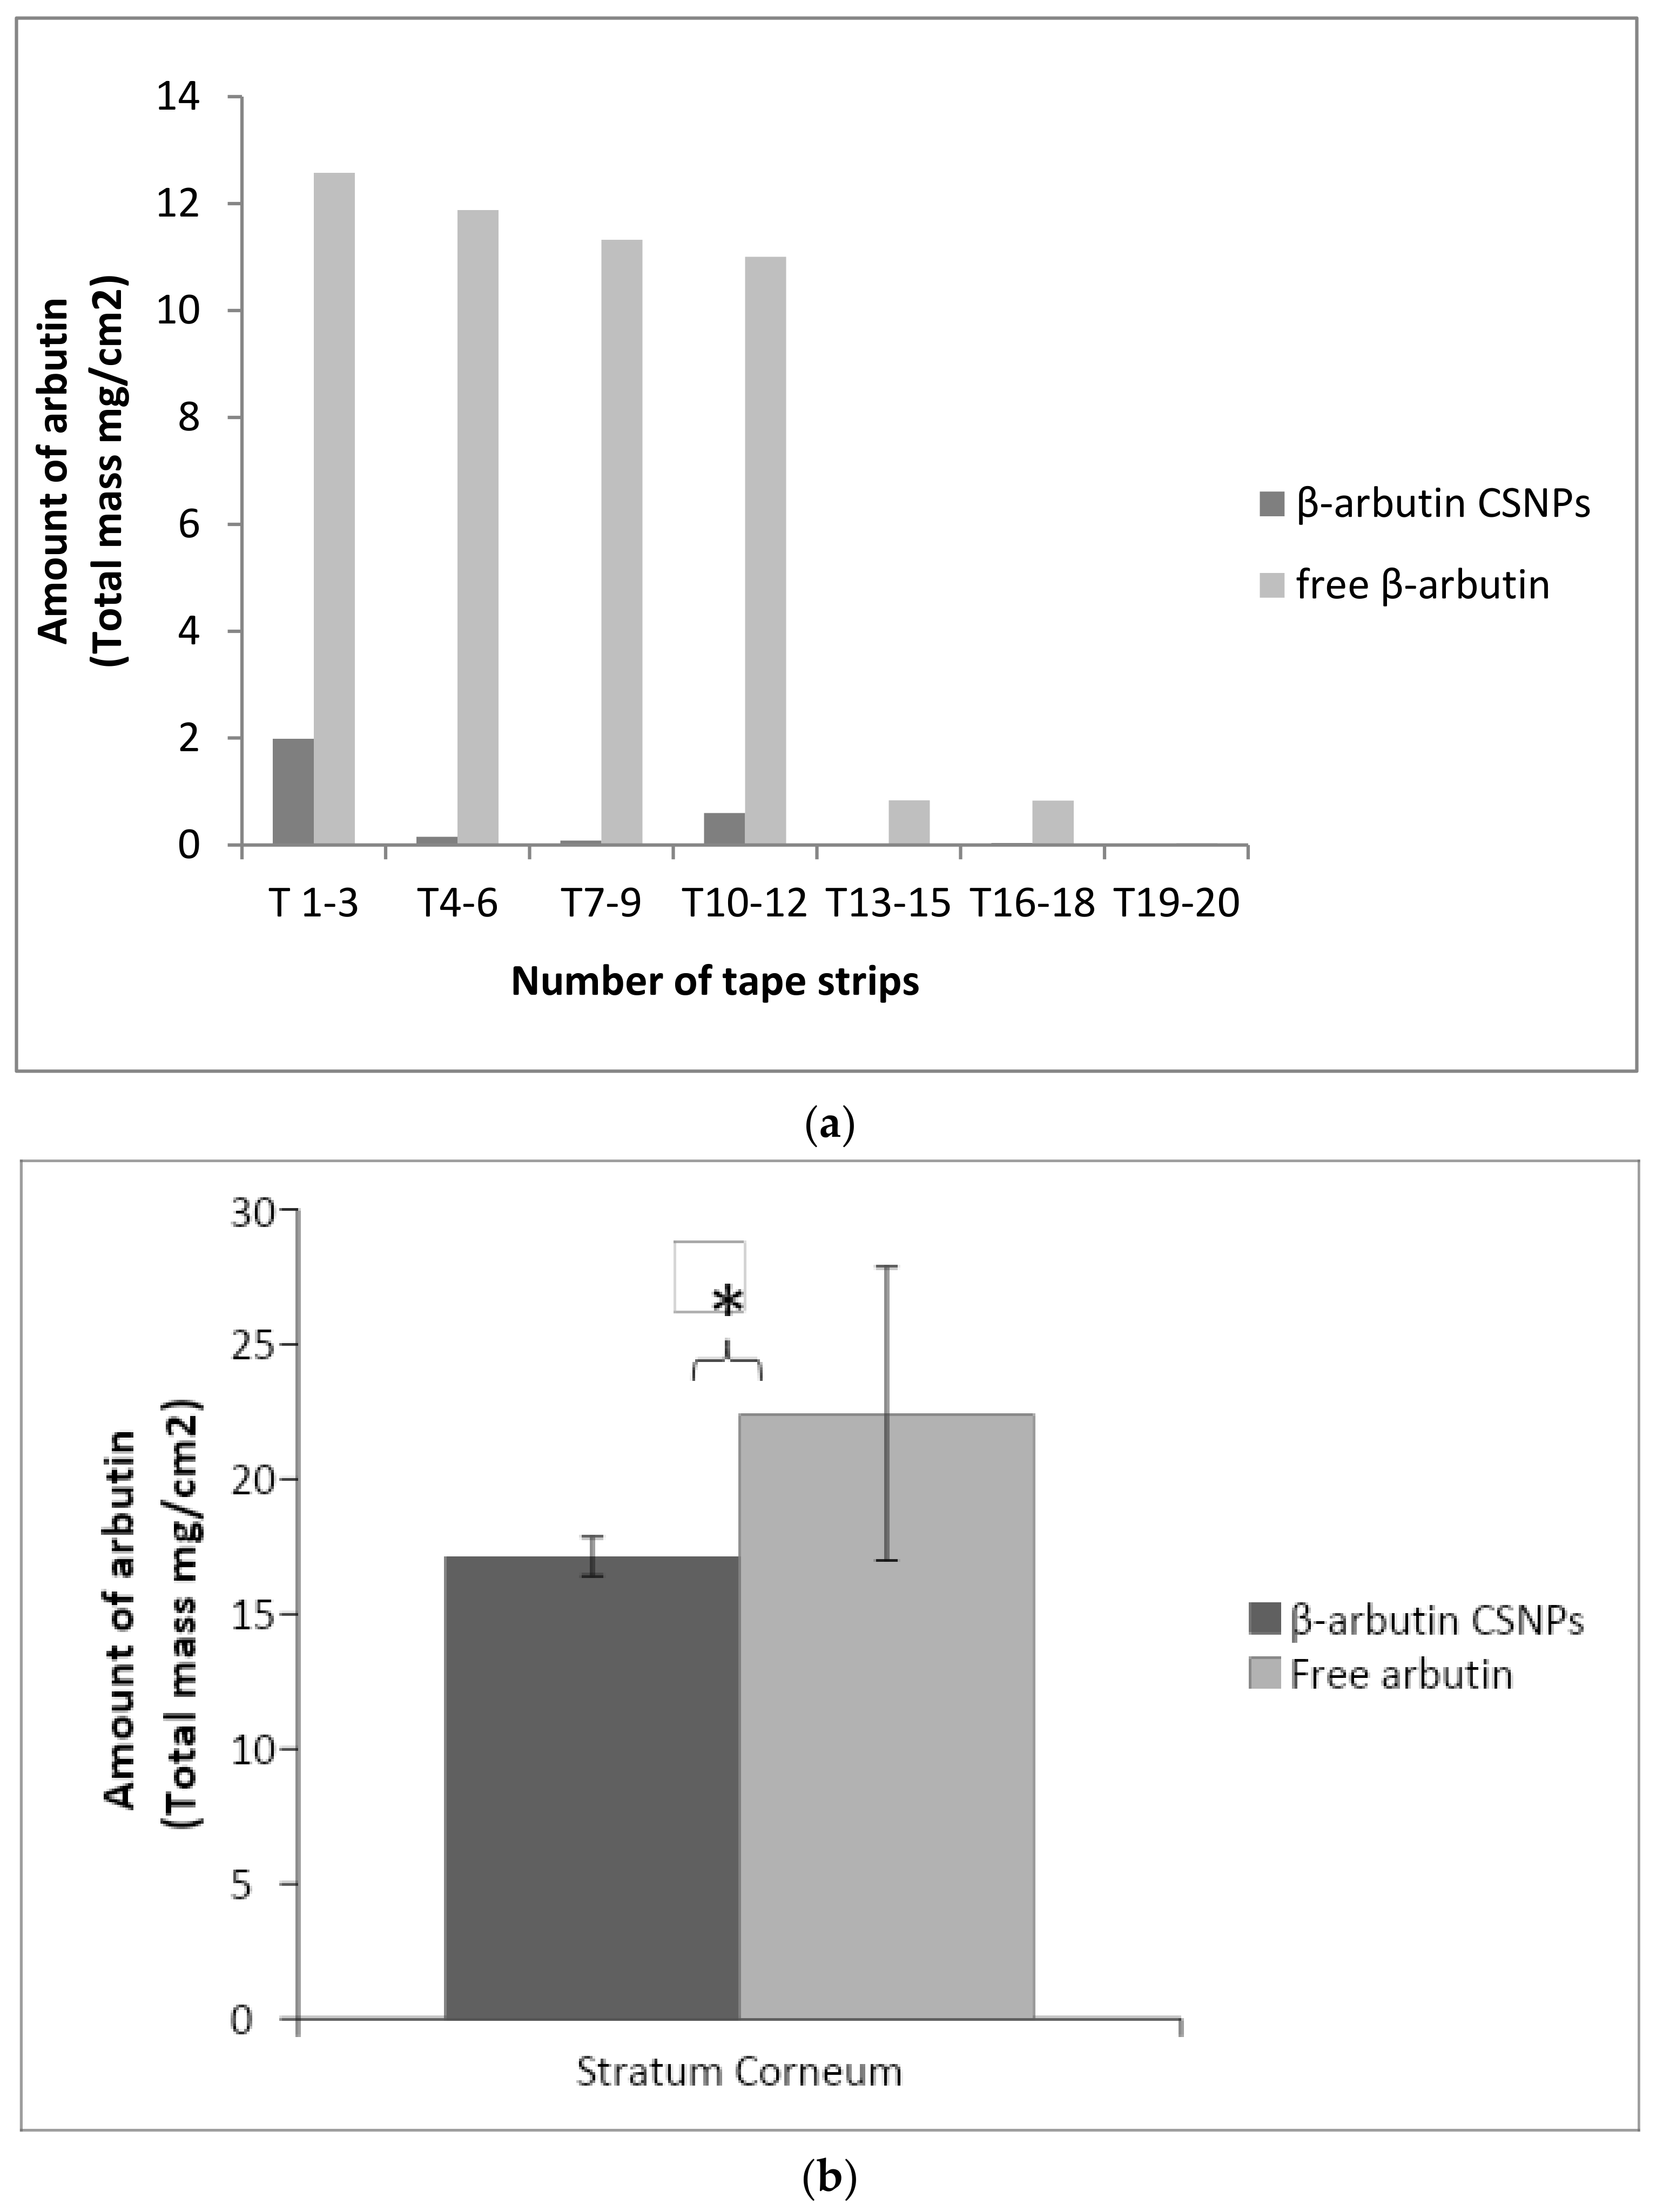

3.8. In Vitro Penetration Study